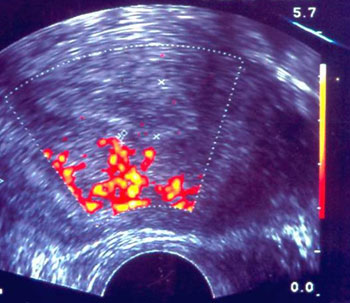

Εικόνα 6. Η αιματική ροή

στους ενδομήτριους κλάδους της μητριαίας αρτηρίας (τοξοειδείς, ακτινοειδείς,

σπειροειδείς) είναι εμφανής με τη μέθοδο της Power Doppler υπερηχογραφίας. Εκφράζεται

υπό μορφή κυμάτων που εκπέμπονται από την περιοχή του μυομητρίου μέχρι και 3

χιλιοστά από τη βασική μεμβράνη του ενδομητρίου. Το ενδομήτριο εδώ εμφανίζεται

ανώριμο (τριζωνικό και υποηχοϊκό), ανέτοιμο για εμφύτευση.